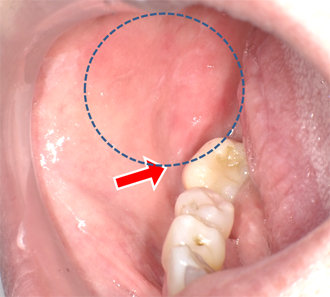

大学病院で前がん病変と診断され、治療法がないということで受診された頬粘膜に発赤とびらんを認める

-